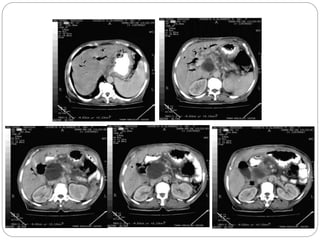

CT Findings typical of pancreatitis include:

1. An enlarged pancreas with infiltration of the

surrounding fat

2. Peripancreatic fluid collections can often be

seen

3. Pseudocysts, (encapsulated fluid

collections containing pancreatic secretions,

are later complications of pancreatitis)

Notice the peripancreatic stranding (bars) as well

as the fluid thickening of the interfascial space